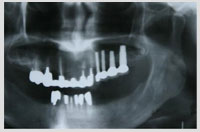

症例2 上顎奥歯 サイナスリフトを伴う症例 年齢50歳 女性

初診時のご希望

・左上の奥歯がないのですが義歯は使いたくない

・他院では骨があまりにも薄いのでインプラントは出来ないと断られた

・奥歯が終わったら前歯も壊れそうなので抜いてインプラントにしたい